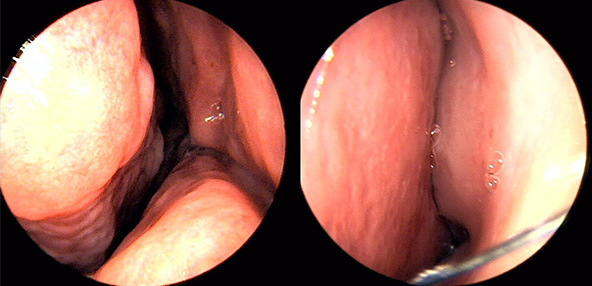

※ 비중격 비염 수술 후 생길 수 있는 부작용으로는 출혈, 감염, 염증이 있을 수 있습니다.

본 사진은 의료기관에서 진료를 본 환자이고, 전후 사진 인물이 동일인이며,동일조건에서 촬영이 되었습니다.